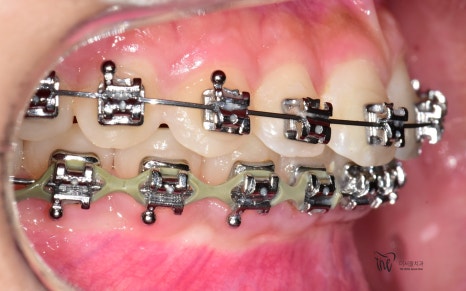

이 분은, 교정장치를 달고 있는 상태로 오셨는데

어딜가더라도, 이 장치를 제거해달라 요청을 하여도

그 요청을 받아주는 곳이 없다 말씀을 하셨습니다.

그럴 법 한게, 책임을 지기 싫거든요.

근데, 저는 이 교정을 제가 이어서 쭈욱

진행을 해드리려고 했었는데 환자께서는

‘괜찮아요 선생님, 저 그냥 마지막 단계만

잘 끝내고 그냥 교정기를 떼고 싶어요.’ 라

말씀을 하셨습니다.

근데, 이거 다 끝난게 아닙니다.

아직, 치아 얼라이먼트가 완성이 되지 않았습니다.

그러면서, 치아 레벨링이 완성이 되질 않았습니다.

레벨링 이라는 것은 위, 아래 치아들을 동시에

놓고 봤을 때의 가지런함을 뜻합니다.